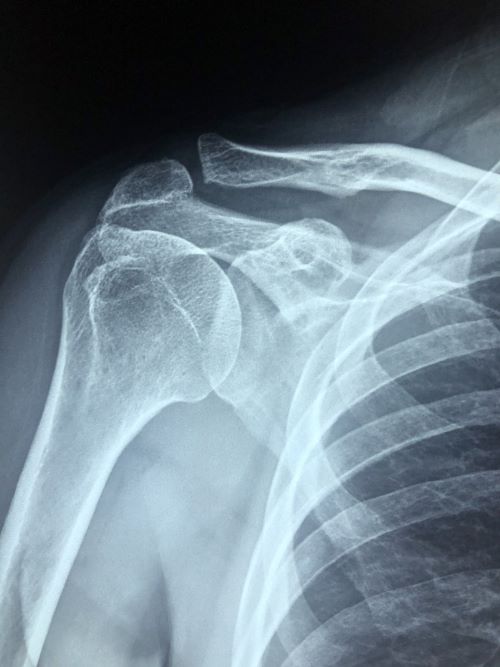

① 회전근개 질환

어깨를 움직이게 해주는 힘줄(회전근개)이

퇴행성 변화나 외상으로 손상된 경우이다.

팔을 들어올릴 때 통증이 심하고, 특정 각도에서 움직임이 제한된다.

② 오십견 (유착성 관절낭염)

특별한 외상이 없음에도 불구하고

어깨 움직임이 점점 줄어들고,

밤에 통증이 심해지는 것이 특징이다.

③ 석회화건염

힘줄 부위에 석회가 침착되면서

극심한 통증을 유발하는 질환이다.

급성일 경우, 팔을 움직이지 못할 정도로 통증이 심하다.

하지만 정확한 구분은 영상 검사(MRI, 초음파 등)를 통해

전문가의 진단을 받는 것이 필수이다.